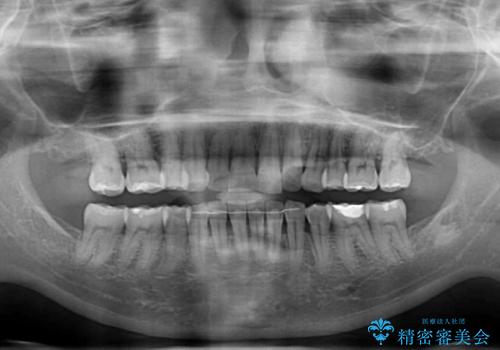

- 上の前歯の出っ歯を治したいとのことで来院された患者様です。

後戻りによる再矯正というもともあり、インビザラインを希望されていました。

上顎の歯は後方移動とIPR(歯と歯の間を削る)によって口元が引っ込むように、下顎は歯列全体の拡大とIPRによって上顎とバランスよく咬み合うように設計し、インビザラインにより治療を行うこととしました。

治療を開始して暫くして、勤務先から2年以上帰国することができず、それまでの移動がほとんど後戻りしてしまい、帰国後に再度後戻りをリカバリーするための治療を行うこととなりました。

5年以上の治療期間がかかりましたが、気になっている部分を改善することができました。